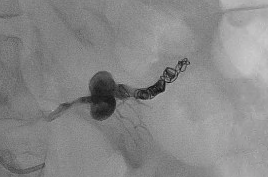

@dpduncanMD_IR @VUMCradiology @UCSDRadRes @Quinn_Meisinger @myliuMD @shelbyfrantzMD @iRadRock @MinaMakaryMD @theIIMD @IRdocAndy @JohnDoIR @RmelikMD @TWongMD @DRimaniIR @danbrownIO @ecemmons @CBoonie_nanoIR @Ajairam_MD_IR pubmed.ncbi.nlm.nih.gov/35907643/ I’ve always thought this was a great case. Great technique by the IR to boot!